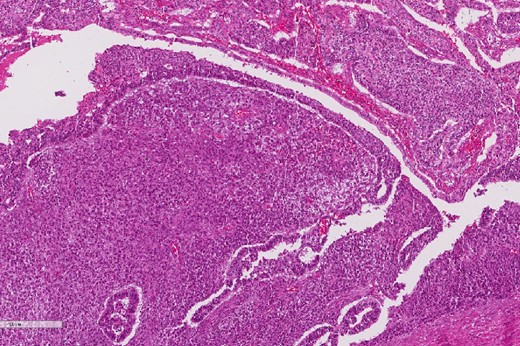

A review of the previously resected esophageal tumor revealed the presence of both epithelial and sarcomatous components. The epithelial component was composed of moderately to poorly differentiated adenocarcinoma, while the sarcomatous component showed hyperchromatic round to spindle cells with scant cytoplasm and frequent mitoses (Figs 3–6). The intrathoracic tumor showed a similar morphology as the sarcomatous component of the esophageal tumor, with focal rhabdomyoblastic differentiation (Fig. 7). The latter was strongly positive for desmin, myogenin, and MyoD1 and was focally positive for synoplastin, CD56, CD 10, and FL1.

High power magnification of the esophageal tumor showing the adenocarcinoma intermixed with spindle cell sarcoma.